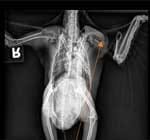

Images 48 and 49: 6- year-old male budgerigar with a Sertoli-cell tumor (tumor of the ovaries or testes). Note the soft tissue mass in the mid-coelom (main body cavity) and polyostotic hyperostosis (enlargement and thickening of the long bones). Red arrows point to long bones; black arrow to soft tissue mass (image courtesy H. Bowles) 7